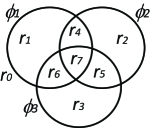

In the continuous domain, Vese and Chan (2002) extended their level set-based method to multiphase level sets. To segment objects, their method needs level set functions. The number of regions is upper-bounded by a power of two (Figure 12(a)). ¡ltx:note¿Therefore, the actual number of regions the method yields is sometimes not clear as it depends on the image and the regularization weights. This issue happens specifically when the number of regions of interest is less than .¡/ltx:note¿ Mansouri et al. (2006) proposed to assign an individual level set function to each object of interest (excluding the background), i.e. their method needs non-overlapping level set functions to segment objects (Figure 12(b)). Chung and Vese (2009) proposed another method that uses a single level set function for multi-object segmentation. They proposed to use different layers (or levels) of a level set function to represent different regions as opposed to just using the zero level set (Figure 12(c)). None of the aforementioned continuous methods guarantee a globally optimal solution for multi-label problems. Pock et al. (2008) proposed a spatially continuous formulation of Ishikawa’s multi-label problem. In their method, the non-convex variational problem is reformulated as a convex variational problem via a technique they called functional lifting. They used the following energy functional